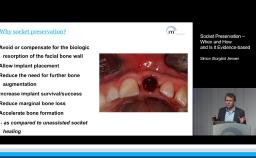

When severely atrophic jaws are encountered, many different implant-prosthetic approaches have been used to address this condition. The more-aggressive protocols call for bone grafting followed by placement of standard-diameter endosseous implants. This presentation focuses on clinical applications of implants with reduced dimensions. In the setting of reduced alveolar bone height, short dental implants offer clinicians a pragmatic option to facilitate prosthetic restoration when confronted with anatomic limitations. When short implants are employed, implant design and surface properties become very important. Likewise, diameter-reduced implants must be used judiciously to avoid complications.